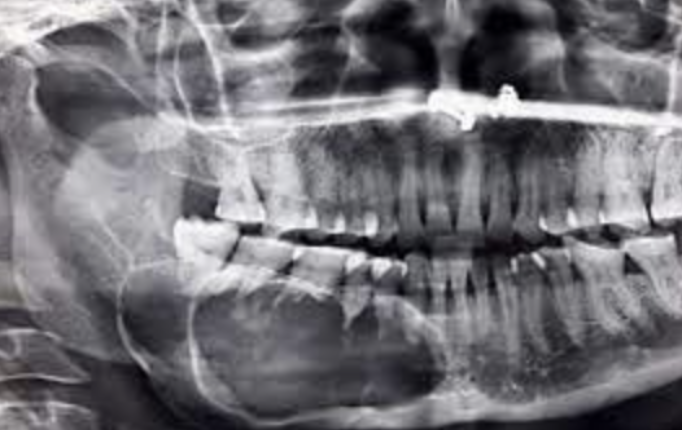

Q

Differential diagnosis for the following image:

A

Langerhan cell histiocytosis (because the teeth are floating in air)